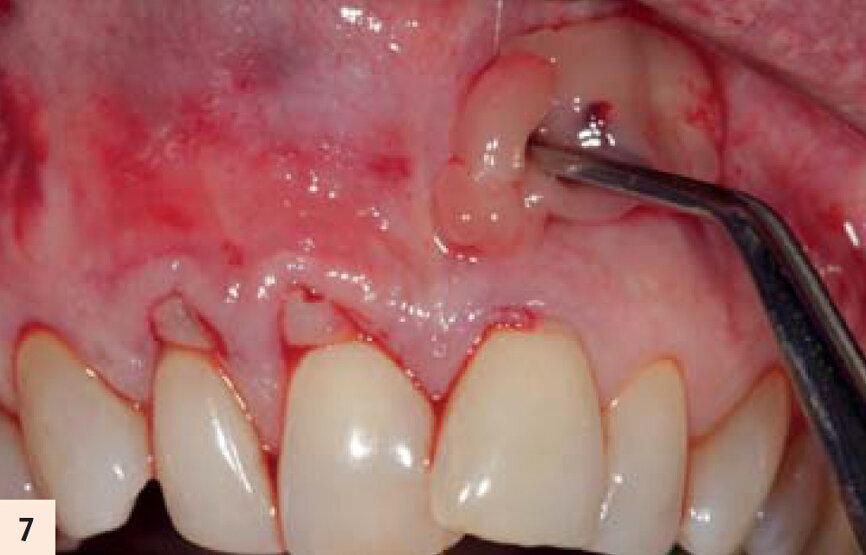

figure 7 : Mise en place d’une membrane d’A-PRF. La technique « distal-mesial backpack » garantit le remplissage total par des membranes d’A-PRF de la poche créée. Trois ou 4 membranes sont recommandées par couple de dents à traiter.